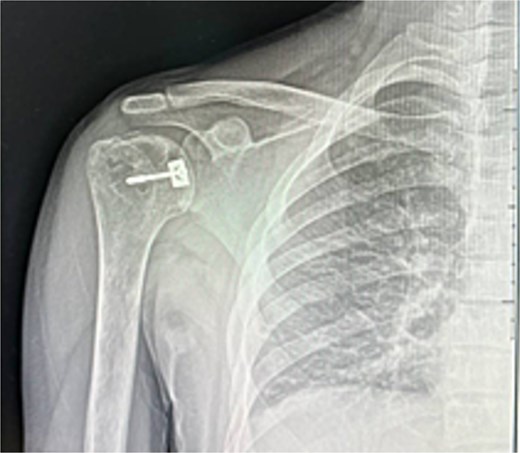

He was counseled for open reduction and modified McLaughlin procedure. Through a deltopectoral approach, open reduction was achieved, and subscapularis with lesser tuberosity was transferred to the defect and fixed with a partially threaded screw. Postoperative X-rays showed satisfactory reduction (Fig. 3). He was discharged the next day in an external rotation brace.

At 2 weeks, the wound healed well, and rehabilitation began at 4 weeks. At 6 weeks, he achieved 120° forward flexion, 160° abduction, and improved external rotation. At 2 months, flexion increased to 140°, abduction to 170°. By 6 months, he reached 160° flexion, 170° abduction, with minimal external/internal rotation lag (Figs 4–6).